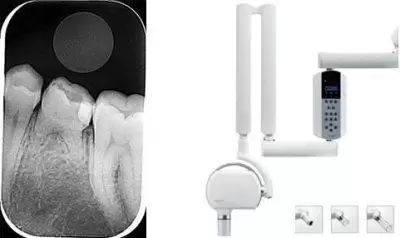

Radiografía Periapical

Es un tipo de radiografía intraoral con la que obtenemos la imagen de uno o varios dientes para su diagnóstico.

Es un procedimiento fácil, rápido y no causa molestias al paciente. Se realiza en el box dental con collarín plomado para proteger la glándula tiroides.